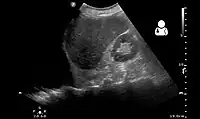

Other methods

Ultrasonography may be used to detect hemothorax and other pleural effusions. This technique is of particular use in the critical care and trauma settings as it provides rapid, reliable results at the bedside.[23] Ultrasound is more sensitive than chest x-ray in detecting hemothorax.[25] Ultrasound can cause issues in people who are morbidly obese or have subcutaneous emphysema. When CT is unavailable in the current setting or the person cannot be moved to the scan, ultrasound is used.[3]

Ultrasound scan of the chest showing a left-sided hemothorax